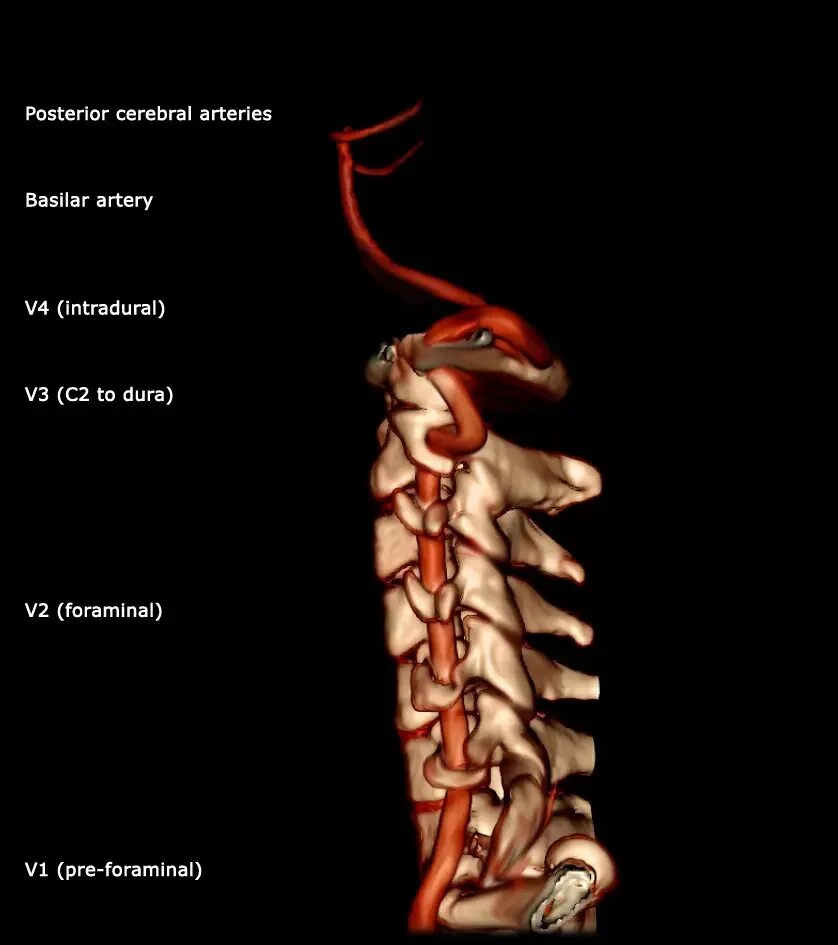

Интракраниальные сегменты